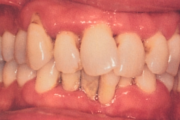

Krooniline parodontiit

Krooniline parodontiit on mikroobide poolt põhjustatud hammaste tugikudede põletik, mille tulemusena tekib progresseeruv alveolaarluu (nähtav röntgenograamil) ja periodontaalligamendi destruktsioon, igemetaskute moodustumine, igeme retsessioon või mõlemad kahjustused kombineeritult. Loe edasi »